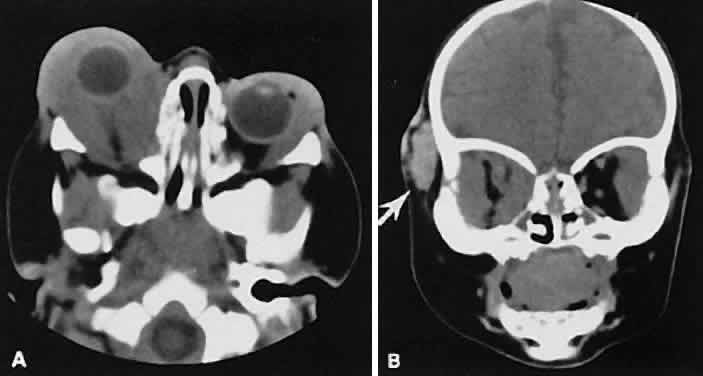

Radiographic evaluation can show either infiltrative or circumscribed masses. Some tumors display a predilection for metastasizing to certain structures, such as prostate carcinoma to bone and cutaneous melanoma to EOMs (Fig. 21). Evidence of bilateral disease at presentation ranges from 7% to 9%, with the prime example being neuroblastoma.71

Fig. 21. A. Axial view shows bilateral involvement from metastatic breast carcinoma. An amorphous infiltrative soft-tissue mass is more apparent in the right orbit, which encases the globe, producing clinical and radiographic enophthalmos. Cutaneous melanoma metastatic to the superior rectus muscle is depicted on axial (B) and coronal (C) views. A locally enhancing and asymmetric enlargement is restricted to the right superior rectus muscle. These features distinguish this lesion from Graves' orbitopathy.